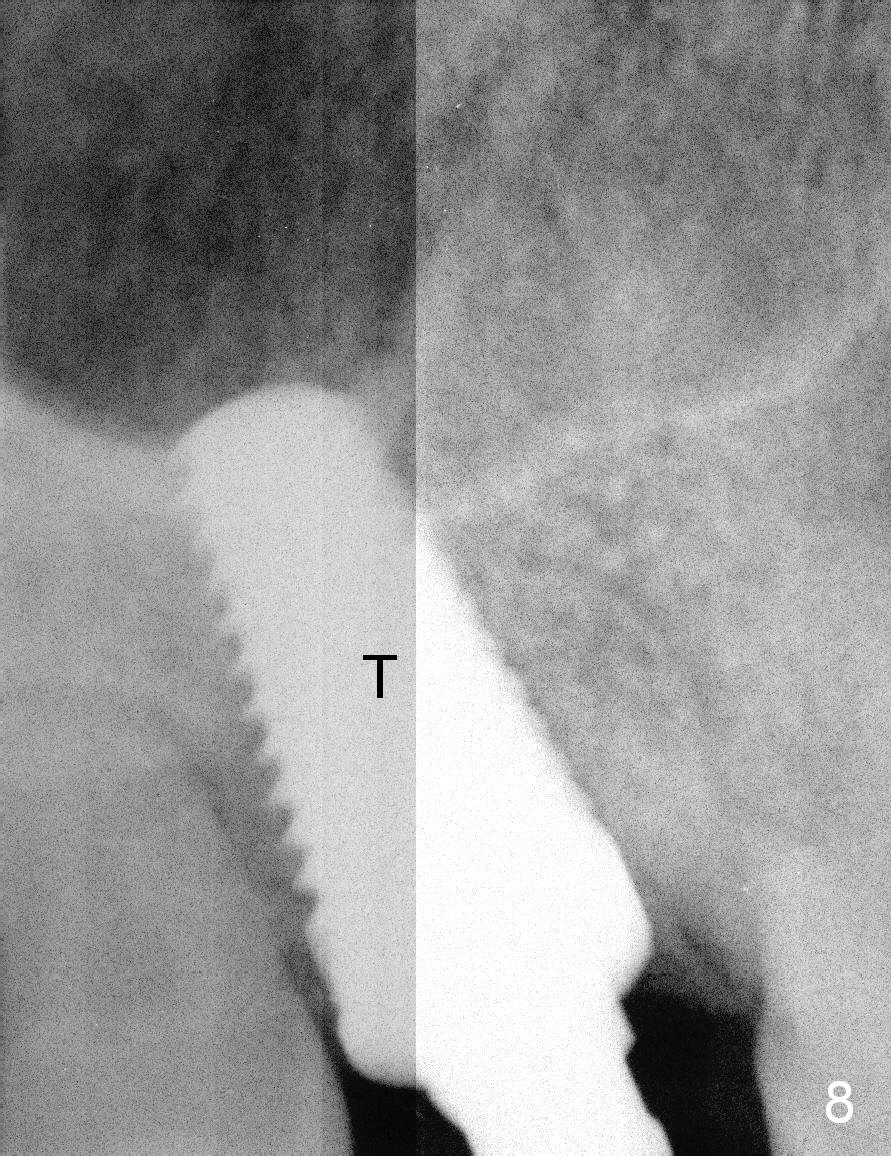

Osteotomy for immediate implant is initiated with a 2 mm pilot drill (Fig.6b red arrow) in the coronal end of the buccal slope of the septum (center of the socket). Once the drill gets initial penetration, the trajectory changes to the long axis of the tooth (Fig.6c). Then PA is taken with a parallel pin (Fig.7). It appears that the depth is not enough; there is bone apical to the pin. As osteotomy increases in diameter, burs may be deviated buccally due to the septal buccal slope (to be discussed below). With longer osteotomy, the deviation may be less. Osteotomy is deepened (Fig.6d). From this moment on, nose blowing test is done after each step. The result is all negative. As drill diameter increases, they do deviate buccally (Fig.6e arrow), since there is less bone contact buccally than lingually (compare Fig.6e,f). With the same reason, smaller tapered taps (Fig.6g pink, 5 and 6 mm) tend to be mobile buccally (arrow). When a large tap (7 mm) is inserted (Fig.8), there is no buccal mobility. It appears that the tap contacts more of the buccal plate (Fig.6h), but the coronal end of the tap is buccal (Fig.6i, pink circle). At each step of osteotomy, the coronal end of a bur or tap should be pushed as lingual as possible so that the final tap is favorable for restoration (Fig.6j). Sinus lift is done (Fig.6k red circle; Fig.9 *) before placement of 7x17 mm implant (I, >60 Ncm). Since the palatal socket is not associated with implant stability, it is closed by collagen plug (Fig.6l, blue area). As extra precaution, bone graft is placed around the coronal portion of the tissue-level implant (Fig.6l red circles), followed by collagen dressing.